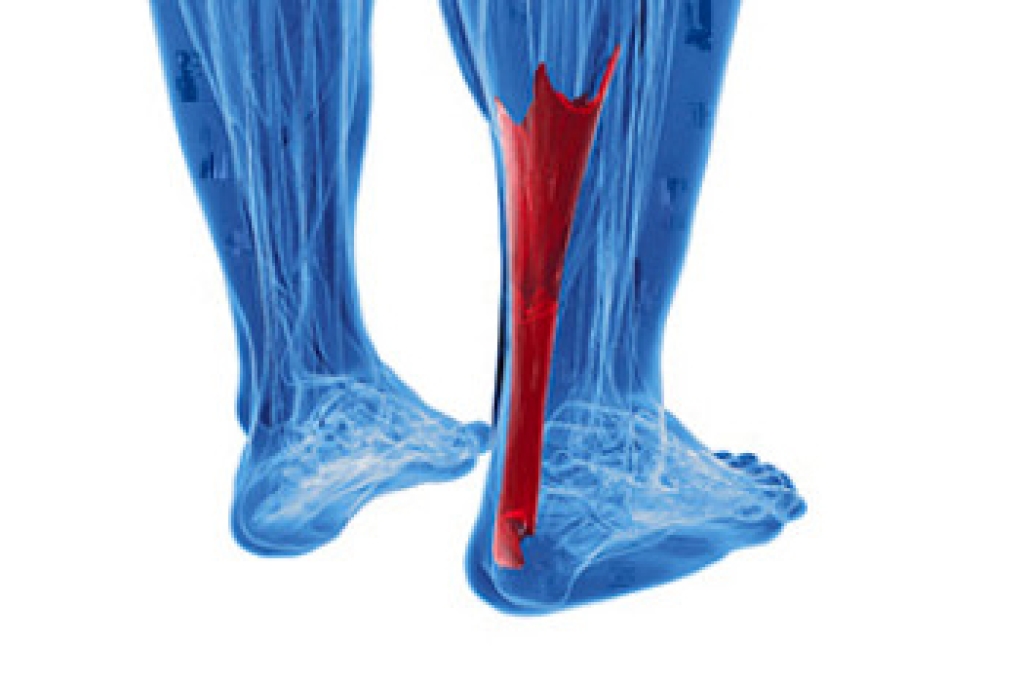

Dealing With Achilles Tendonitis

The Achilles tendon connects the heel to the bones of the leg. When it becomes irritated or swollen, inflammation may set in that causes a painful condition known as Achilles tendonitis. Other symptoms include stiffness and soreness in the heel, a crackling sound when the ankle moves, pain when the foot is extended, and weakness in the affected leg. Achilles tendonitis is common among athletes whose sport or activity puts particular stress on the heel, such as running, jumping, basketball, dancing, skiing, or figure skating. A walking boot or cast may be necessary for stability, and custom orthotics may help to keep the injury from recurring. In severe cases, surgery may be required. Seeing a podiatrist is a wise way to find out the best treatment options to combat this condition.

Achilles tendon injuries need immediate attention to avoid future complications. If you have any concerns, contact one of our podiatrists of Dr. Jeffrey J. Betman & Associates . Our doctors can provide the care you need to keep you pain-free and on your feet.

What Is the Achilles Tendon?

The Achilles tendon is a tendon that connects the lower leg muscles and calf to the heel of the foot. It is the strongest tendon in the human body and is essential for making movement possible. Because this tendon is such an integral part of the body, any injuries to it can create immense difficulties and should immediately be presented to a doctor.

What Are the Symptoms of an Achilles Tendon Injury?

There are various types of injuries that can affect the Achilles tendon. The two most common injuries are Achilles tendinitis and ruptures of the tendon.

Achilles Tendinitis Symptoms

- Inflammation

- Dull to severe pain

- Increased blood flow to the tendon

- Thickening of the tendon

Rupture Symptoms

- Extreme pain and swelling in the foot

- Total immobility

Treatment and Prevention

Achilles tendon injuries are diagnosed by a thorough physical evaluation, which can include an MRI. Treatment involves rest, physical therapy, and in some cases, surgery. However, various preventative measures can be taken to avoid these injuries, such as:

- Thorough stretching of the tendon before and after exercise

- Strengthening exercises like calf raises, squats, leg curls, leg extensions, leg raises, lunges, and leg presses

If you have any questions please feel free to contact our offices located in Northwest Chicago, Southwest Chicago, and Wicker Park, Chicago, IL . We offer the newest diagnostic tools and technology to treat your foot and ankle needs.